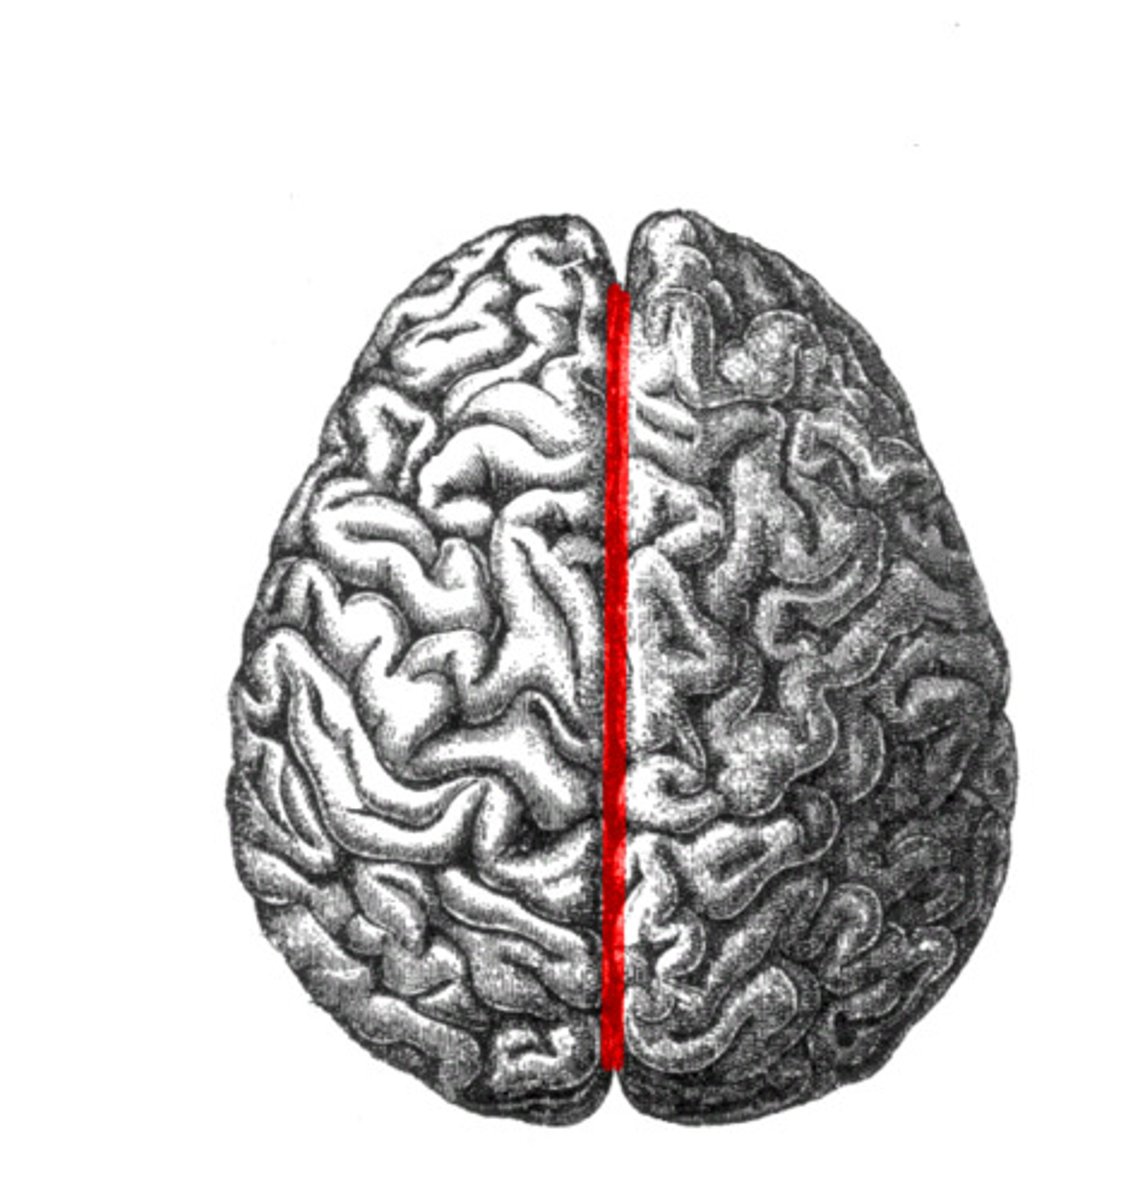

longitudinal cerebral fissure

separates cerebrum into right & left cerebral hemispheres